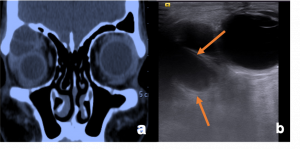

| Lesion | Age/Sex Predeliction | Clinical Presentation | Imaging Findings | Image |

| Preseptal Cellulitis | More common in < 5 years of age group | Lid edema, erythema | CT- shows stranding, swelling, variable enhancement of the preseptal soft tissues anterior to the globe

Sub Periosteal Abscess. Coronal contrast-enhanced CT image of right orbit showing extraconal marginally enhancing fluid collections located superonasally, consistent with subperiosteal abscess. These are present in continuation with opacified right ethmoidal air cells and right maxillary antrum with soft tissue density with hyperdense content. |

| Orbital Cellulitis | More common in > 5 years of age group | Proptosis, chemosis, limitation of EOM, fever | CT- early- eyelid edema and sinusitis

Marked postcontrast enhancement. Inflammation is seen in the medial or superomedial orbit adjacent to the opacified sinus, associated with fat stranding

| Sub periosteal abscess[14] | No age/gender predilection | Collection of subperiosteal fluid causing abaxial proptosis along with other signs of cellutlitis | CT- shows hypodense, convex collection with ring enhancement present along orbital wall

| |

| Invasive Sino-orbital fungal disease[15] | Immunocompromised (mucormycosis)

Imuunocompetent (aspergillosis) |

Severe limitation of EOM with associated chemosis and blepharoptosis.

In mucormysosis, very acute progression of disease with presence of black nasal fliuid, eschar or skin discoloration (characteristic). On fundus examination, CRAO present. In aspergillosis, sub acute progression. |

CT- lobulated soft tissue msses, opacification of paranasal sinuses with high attenuation content with enhancing adjacent orbital soft tissue

T1- low to high intensity T2- marked hypointensity |